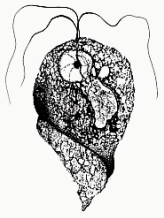

Trichomonas vaginalis (troph)

Giardia (lamblia) duodenalis (troph)